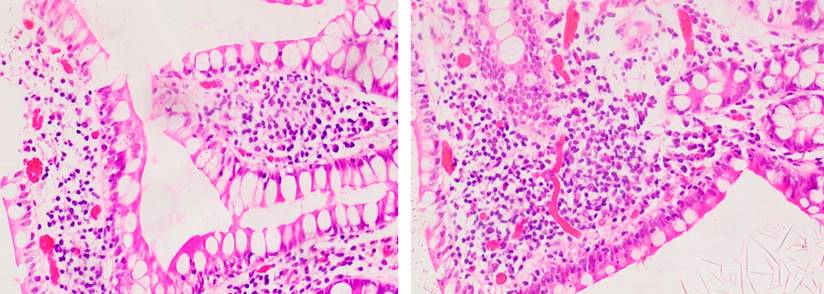

Se realizó una esofagogastroduodenoscopia que mostró gastropatía eritematosa antral y colonoscopia total con evidencia de úlcera de 10 mm de bordes regulares con fibrina a los 3 cm de la anastomosis coloentérica, úlcera de 12 mm de bordes regulares con fibrina a los 5 cm proximales, y dos úlceras de 4 y 7 mm de características similares a los 10 cm proximales a las que se les realizó biopsia del centro y del borde. Adicionalmente, presentó lesiones aftoides escasas en el íleon distal, hallazgos compatibles con ileítis ulcerada con anastomosis coloénterica normal (Figura 1). La biopsia reportó muestras de fragmentos de mucosa ileal no representativas de las úlceras, con un marcado edema de la lámina propia, angiectasias asociadas a infiltrado mononuclear y polimorfonuclear que focalmente erosionan el epitelio superficial, y fragmentos con material fibrinoleucocitario con diagnóstico sugestivo de cambios inflamatorios no específicos (Figura 2).

Figura 2 Hallazgos histopatológicos de muestras de úlceras en el íleon distal. Hallazgos de edema de la lámina propia, angiectasias asociadas a infiltrado mononuclear y polimorfonuclear que erosionan el epitelio distal. Cortesía de Edna Margarita Martínez Ortiz, Patóloga.

La histopatología de la EB a nivel gastrointestinal tiene diversas características, se presenta con hallazgos de infiltrados mononuclear y de mastocitos perivasculares, vasculitis neutrofílica y cambios inflamatorios agudos y crónicos en la submucosa intestinal15. Aunque en el reporte histopatológico de las biopsias tomadas durante la endoscopia no hubo una franca representación de las úlceras en las muestras, los hallazgos de edema de la lámina propia, asociados a infiltrados mononucleares y polimorfonucleares, podrían corresponder a los cambios inflamatorios con los que cursa la EB en el tracto gastrointestinal.